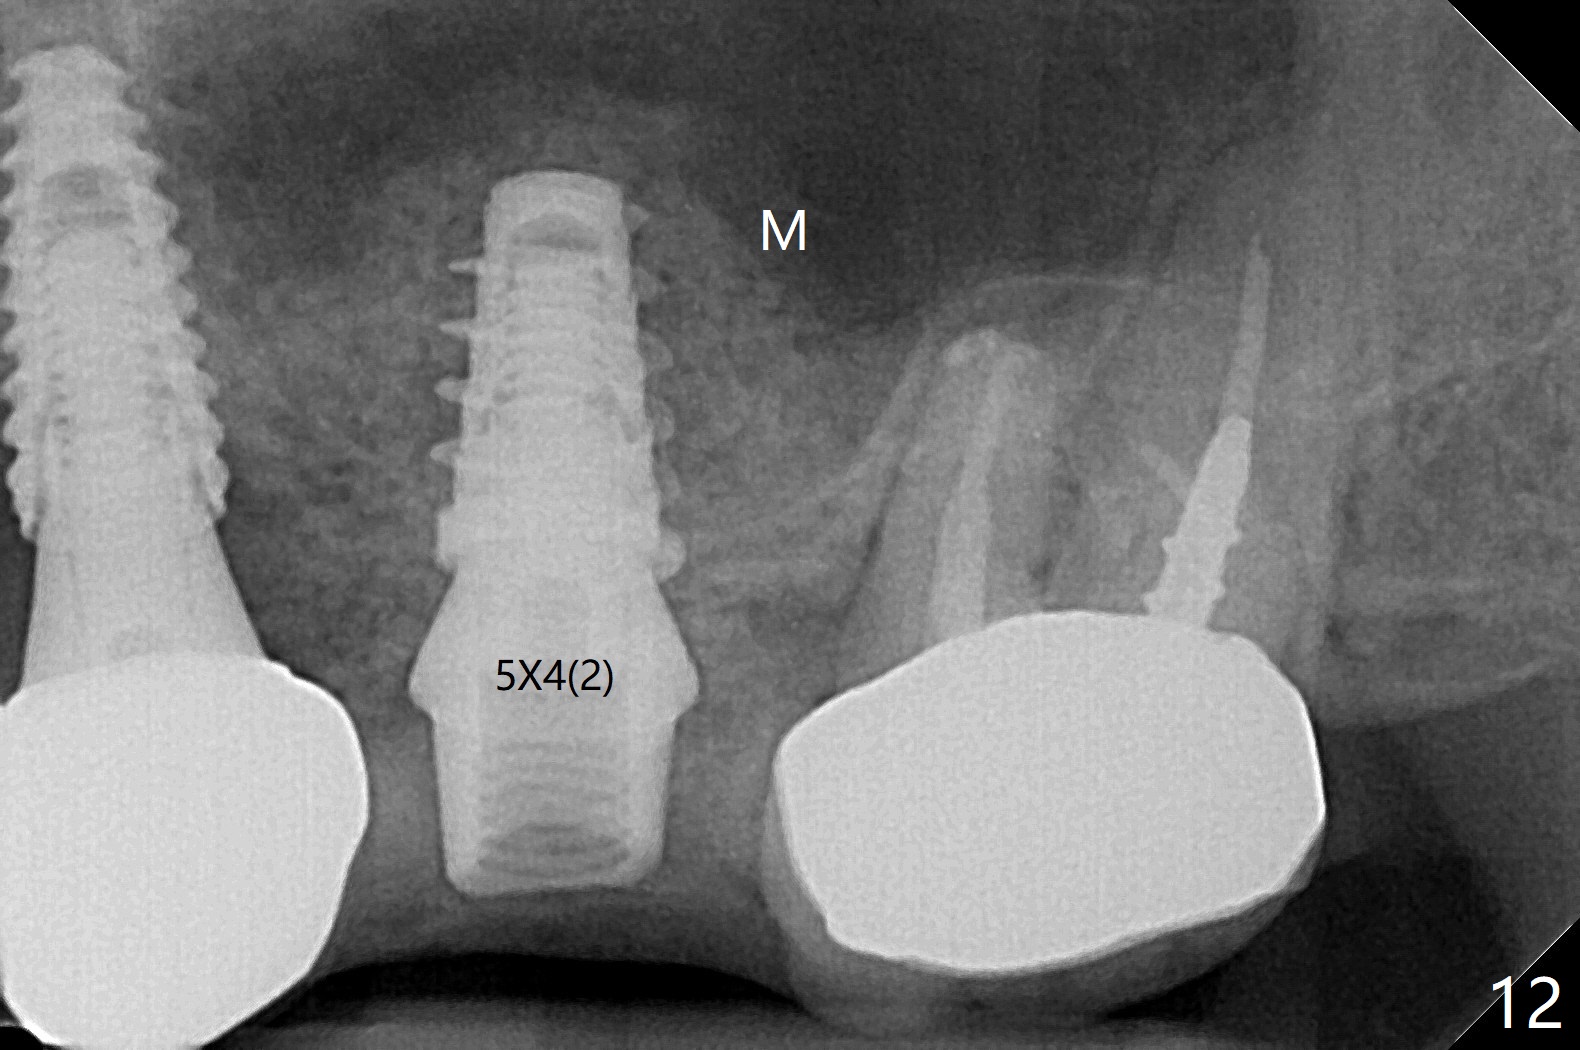

A 68-year-old timid woman is considering implant at #14 twenty months post cementation of #13 and 14 crown (Fig.1). Because of the narrow buccopalatal width (Fig.2 CT coronal section, B: buccal), a 4 mm implant (blue line) seems to be appropriate for the site (Fig.1). After crestal incision and flap reflection, a diamond round bur is used to thin the sinus floor until the bluish membrane is barely visible. An osteotome (Magic Sinus Lifter) is used for penetration. Water lift will be conducted if necessary, considering the already thickened sinus membrane (Fig.3 (CT sagittal section) M). Insert the first PRF membrane, followed by bone graft (not too sticky) repeatedly. Use sensor 1 to confirm lift degree. Try a 4x7 mm dummy FC to test stability. Place a definitive one (probably Magicore) if indicated. Use a second PRF membrane before closure of the wound. After nearly 15 month consideration (including coronovirus), the patient decides to get it done. With incision (Fig.4) and Marking Drill (Fig.5, the sinus membrane barely visible in the middle of the osteotomy (dimple, Fig.6 (black triangle)), the sinus floor does not break upon Magic Sinus Lifter). Later the patient complains of discomfort with tapping. In fact Magic Drill (similar to trephine bur, Fig.7) is used to break into the sinus without membrane perforation (Fig.8). Remember the thick membrane (Fig.2,3). In fact the fractured fragment is attached to the membrane (Fig.9 red lines, green sticky fracture). A small curette is used to further separate the membrane from the bony wall (Fig.10) before insertion of a small piece of PRF and sticky bone. When a 4.5x7 mm dummy implant is incompletely placed with stability (<10 Ncm), the membrane is stretched over the bone graft (Fig.11 M). After removal of the dummy, the major remaining piece of PRF (from 9 cc vial) and more allograft are placed before inserting a definitive implant (same size) with 15 Ncm; still the used to be thick membrane remains intact and stretched (Fig.12 M). The implant is equicrestal buccal, while slightly supracrestal palatal. To prevent implant dislodgement into the sinus and bone graft, a final abutment is placed (Fig.12). The wound is closed with 4-0 PGA, perio glue and perio dressing. The latter dislodges 3 days postop. The wound seems to be healing. No dressing is reapplied.